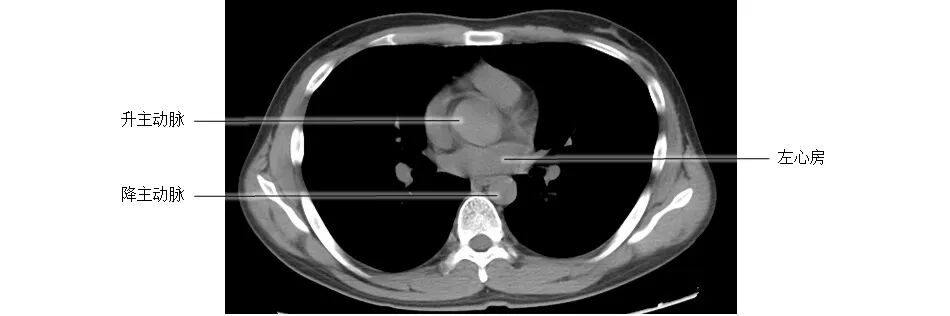

正常胸部CT影像是从横断面显示解剖和病变,可显示的结构包括胸廓、气管和支气管、肺、胸膜、纵隔和膈,CT的重建图像可从各个角度显示胸部解剖情况。不论采用何种图像显示方式,把握基本解剖结构都是必不可少的,一起学习胸部CT肺窗和纵隔窗的正常解剖。

胸部CT纵膈窗